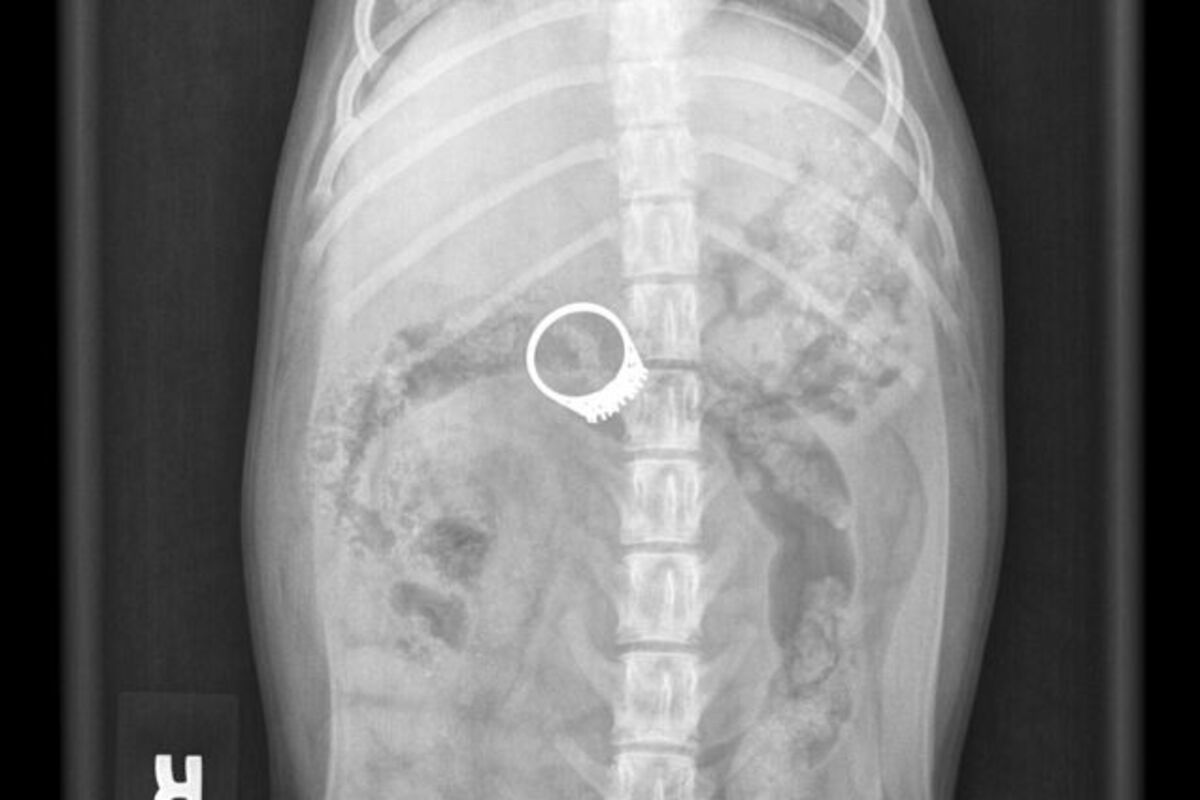

Britanka Karen Vuli je kupila metalni detektor kako bi tražila svoj metalni prsten koji je odjednom nestao sa stola iz njene dnevne sobe.

I našla ga je, gle čuda, u svom šestomjesečnom kučetu Barniju.

Karen je duže vrijeme sumnjala da je upravo njen kućni ljubimac “smazao” prsten sa stola, a detektor je pištanjem potvrdio njene sumnje.

Kako piše britanski Metro, žena je psa odmah odvela kod veterinara gdje su odmah izveli hirurški zahvat kako bi ukonili prsten star skoro 100 godina.

“Taj prsten je mogao da ga košta života. Sva sreća da sam kupila detektor”, kazala je Karen.

Veterinarka je savjetovala Karen, ali i sve vlasnike kučića da drže sitnije predmete podalje od životinja. Barni se trenutno oporavlja kod kuće.